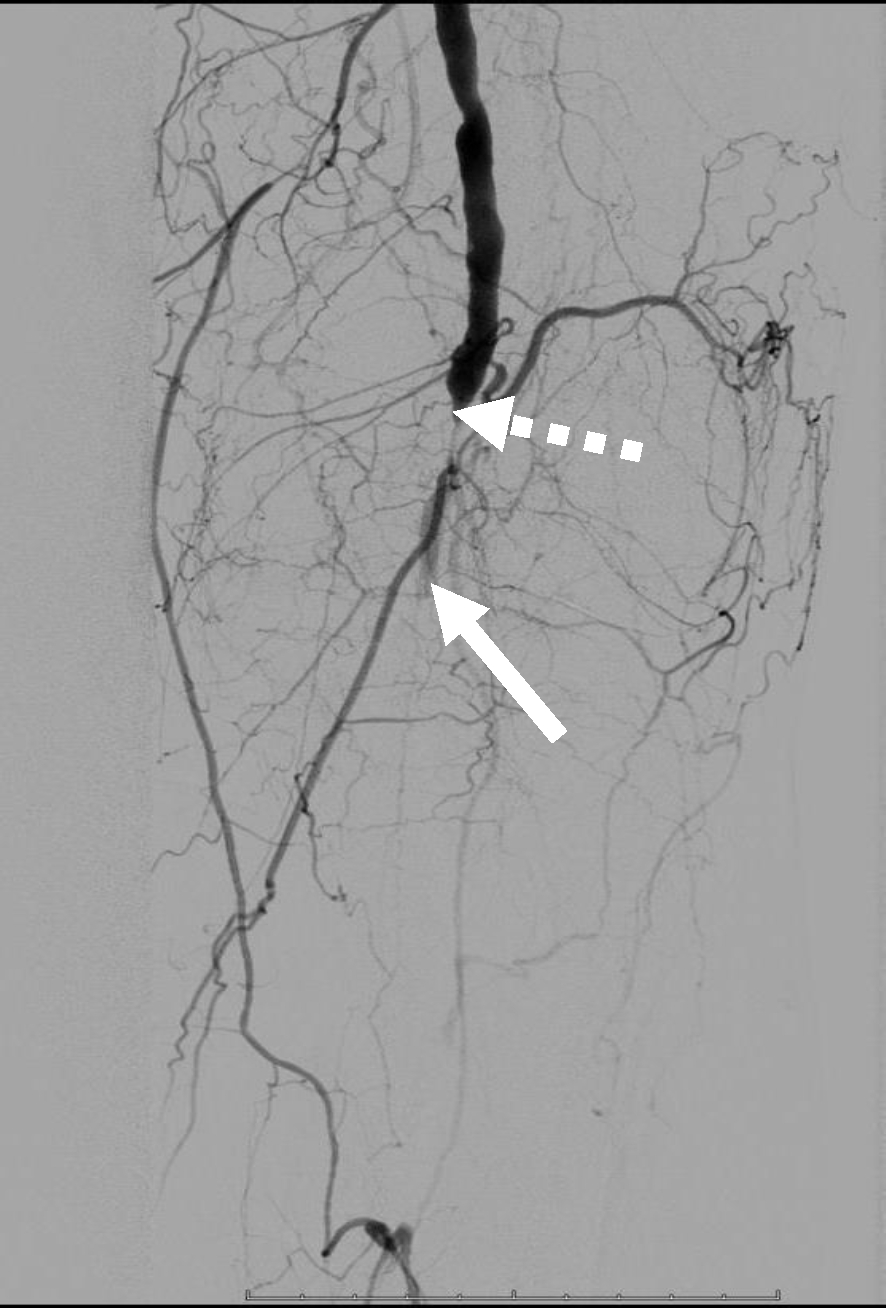

Операция. Транслюминальная баллонная ангиопластика (ТЛБАП) подколенной артерии, тибиоперонеального ствола слева. Под м/а выполнена пункция левой бедренной артерии, установлен интродьюсер 6 Fr. Выполнена селективная ангиграфия артерий левой нижней конечности при которой выявлена субокклюзия подколенной артерии и окклюзия тибиоперонеального ствола (рис. 1). Выполнена ТЛБАП в зоне субокклюзии баллоном 5,0 × 40 мм, давление 8 атм. В области тибиоперонеального ствола ТДБАП баллоном 3,0 мм × 100 мм, давление 10 атм. Получен хороший антеградный кровоток в подколенной, заднебольшеберцовой и малоберцовой артериях (рис. 2). Передняя большеберцовая артерия окклюзирована.

Рис. 2. Ангиограмма больной М. после ангиопластики. Восстановление магистрального кровотока в проксимальном (а) и дистальном (б) отделах голени